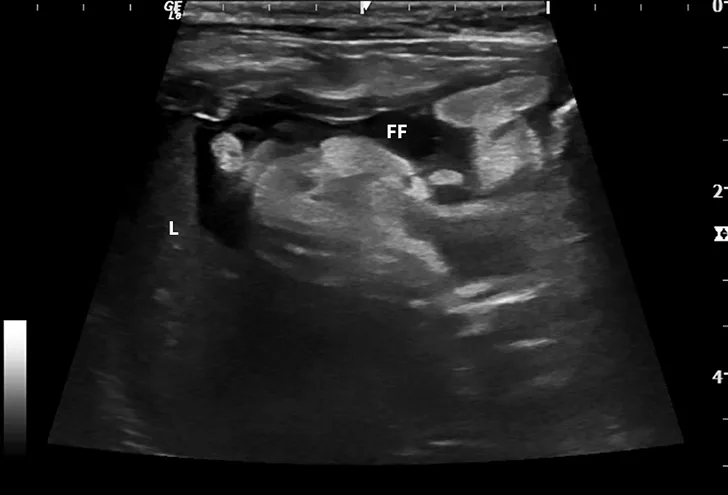

Dry FIP can manifest with organ dysfunction, uveitis, neurologic signs, fever, anemia, and/or lethargy and is caused by granulomas or immune complex deposition. Cats with wet FIP may have ascites or pleural effusion in addition to the aforementioned signs (Figure 1). Clinical presentation can vary from minor to life-threatening and involve almost any organ system.

Ultrasound image showing abdominal effusion in a cat with wet FIP. Anechoic fluid is present between organs, distending the abdomen. FF = free fluid; L = liver; S = spleen; K = kidney